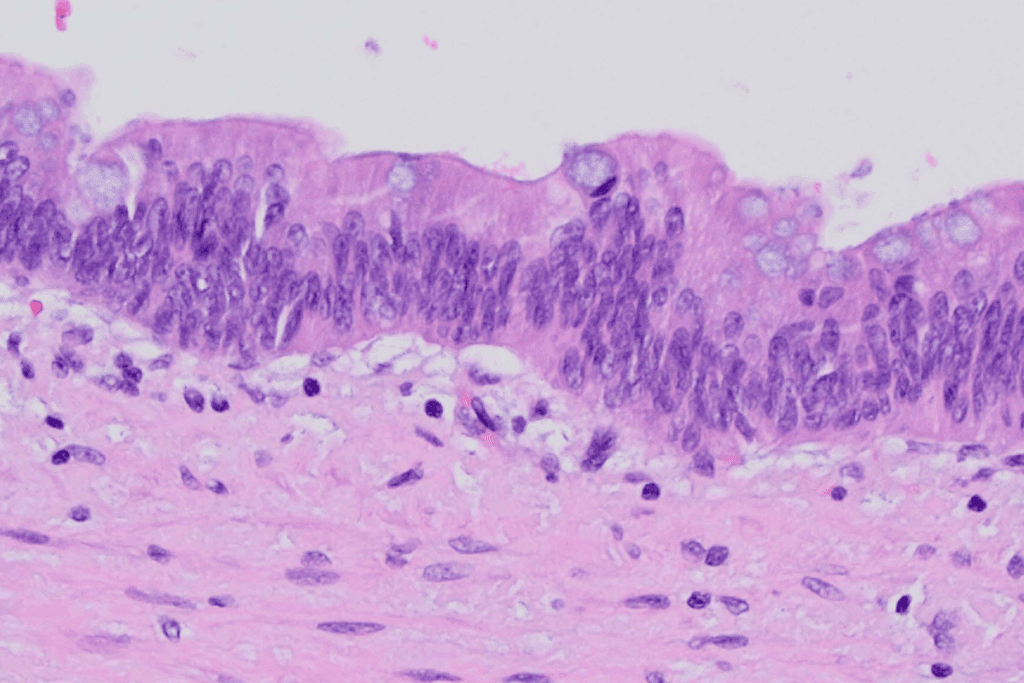

We’ll explore the makeup of the oral epithelium. It’s made of stratified squamous epithelium. This can be keratinized or non-keratinized, depending on its role in the mouth.

Epithelial Layers and Their Composition

The oral epithelium has several layers, each with its own role. These layers include:

- Stratum Basale: The deepest layer, made of cuboidal or columnar cells. These cells help the epithelium grow and repair itself.

- Stratum Spinosum: Several layers of polyhedral cells. They add strength and cohesion to the epithelium.

- Stratum Granulosum: A layer of flattened cells. They prepare cells for the surface layers.

- Stratum Corneum: The outermost layer, made of fully keratinized cells. They protect against damage from the outside.

Together, these layers keep the oral epithelium strong and functional.

The Basement Membrane and Lamina Propria

Underneath the oral epithelium is the basement membrane. It’s a thin, fibrous layer that separates the epithelium from the lamina propria. The lamina propria has collagen and elastin fibers, along with cells like fibroblasts and lymphocytes.

The basement membrane and lamina propria support the oral epithelium. They help with nutrient exchange and support the immune system in the mouth.